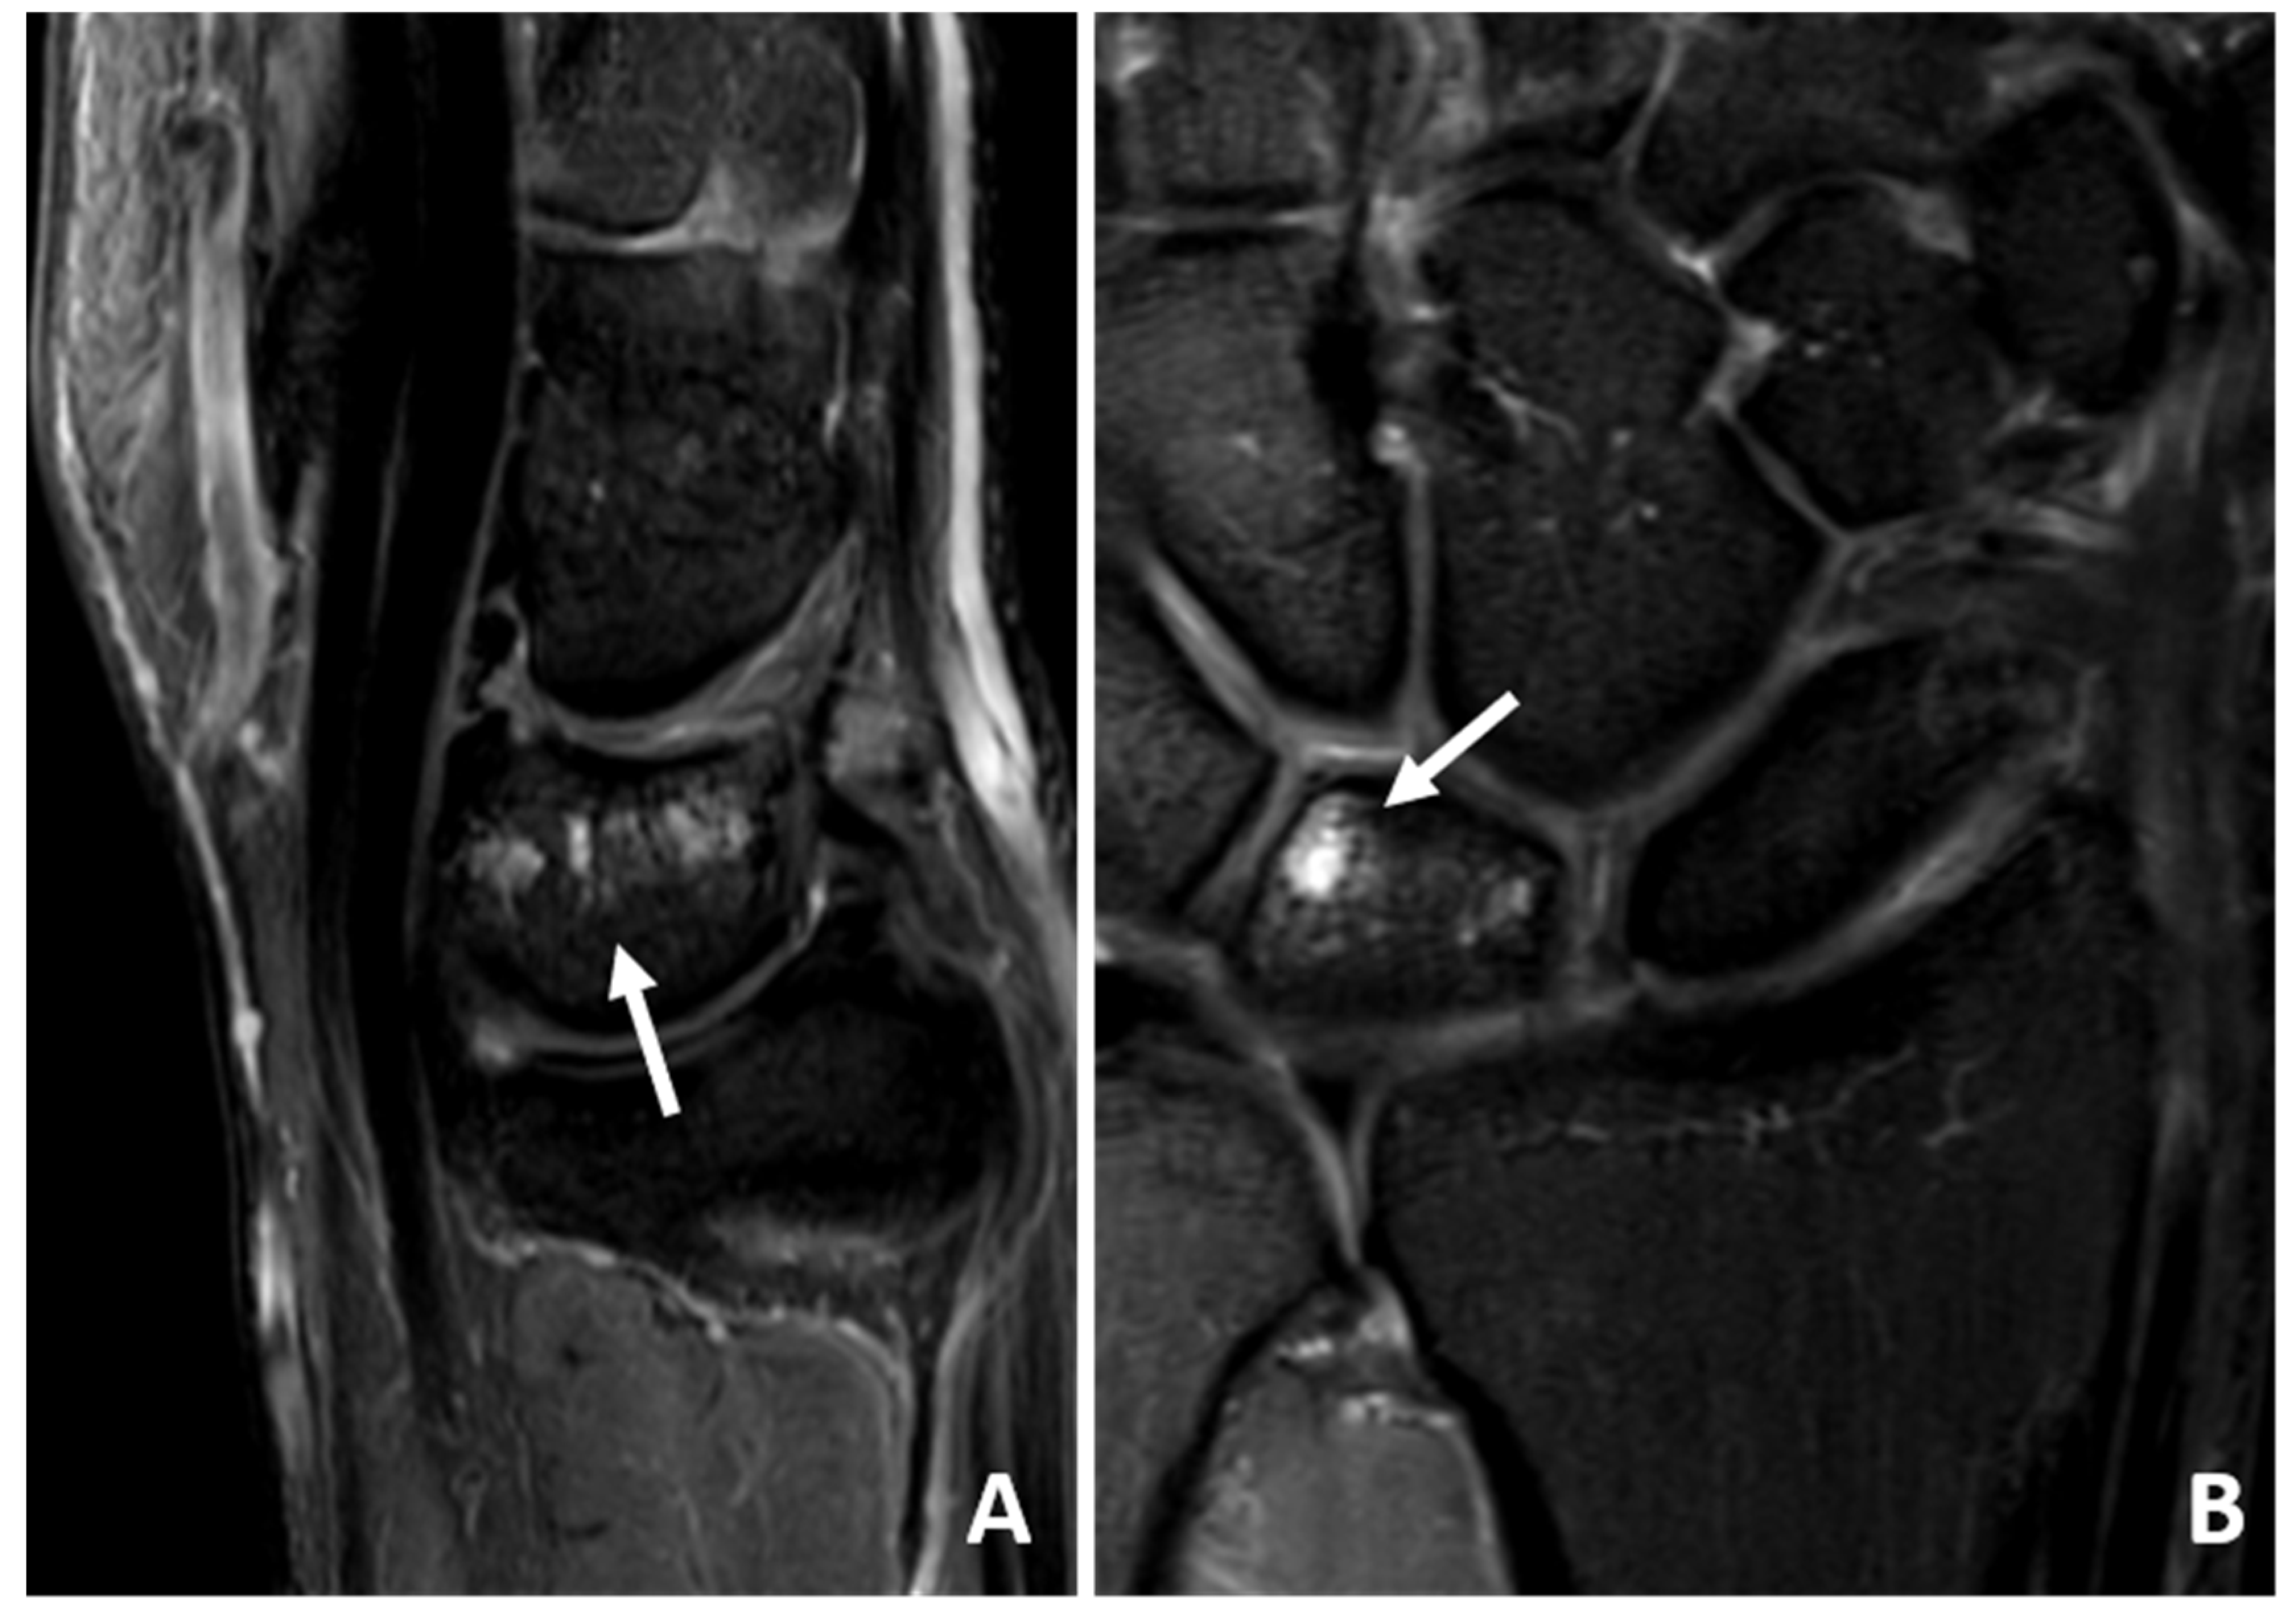

3.4. MRI Scan